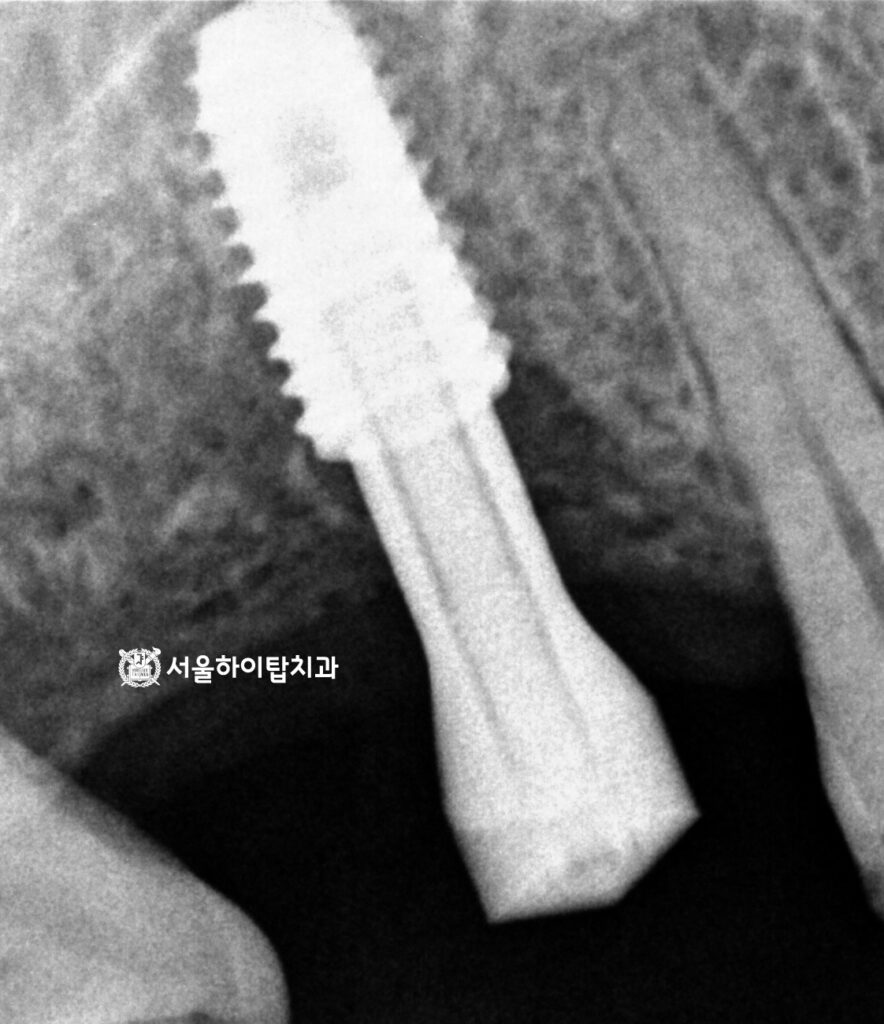

그다음으로 CT 촬영을 통해 식립에 알맞은 위치, 각도, 깊이를 확인하고,

동시에 하지조신경관 등 주변 해부학 구조물을 안전하게 확인하게 됩니다.

수술 완료

정밀한 CT를 통해 나온 데이터에 따라 정확한 위치에 심긴 모습입니다.